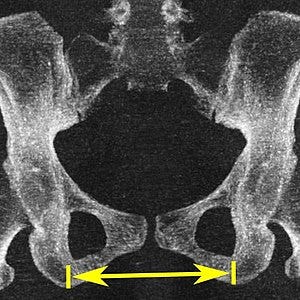

Recent research from France has dropped a bombshell that's got the obstetric world buzzing. A comprehensive study analysing 551 CT pelvimetries revealed something eye-opening: our current "normal" values might be seriously outdated. The researchers found that modern women's pelvic dimensions don't quite match those decades-old textbook numbers we've been faithfully following.

Here's the kicker – the median obstetric transverse diameter they found was 12.41 cm, with the 3rd percentile at 11 cm. These numbers; they represent real outcomes that could reshape how we approach delivery planning.